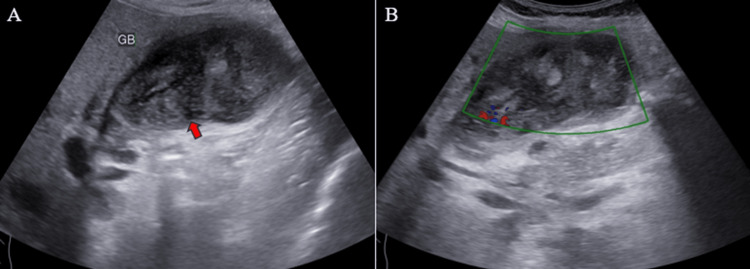

Ultrasound (US) examination revealed bilobar intrahepatic biliary radicle (IHBR) dilatation (Figure 1), and the gallbladder appeared overdistended with large, heterogeneously hypoechoic content devoid of vascularity on color Doppler (Figure 2). The gallbladder wall appeared thickened, measuringapproximately 4 mm. Furthermore, the proximal CBD appeared mildly dilated, measuring 8 mm, with a heterogeneously hypoechoic lesion within the midportion causing its narrowing (Figure 3). Multiple subcentimetric to enlarged necrotic lymph nodes were also observed in the porta-hepatis, periportal, and retroperitoneal regions (Figure 4).

These findings were suggestive of an infective etiology, likely indicative of acute cholecystitis with thick purulent content in the gallbladder and a mass lesion in the mid-portion of the CBD.